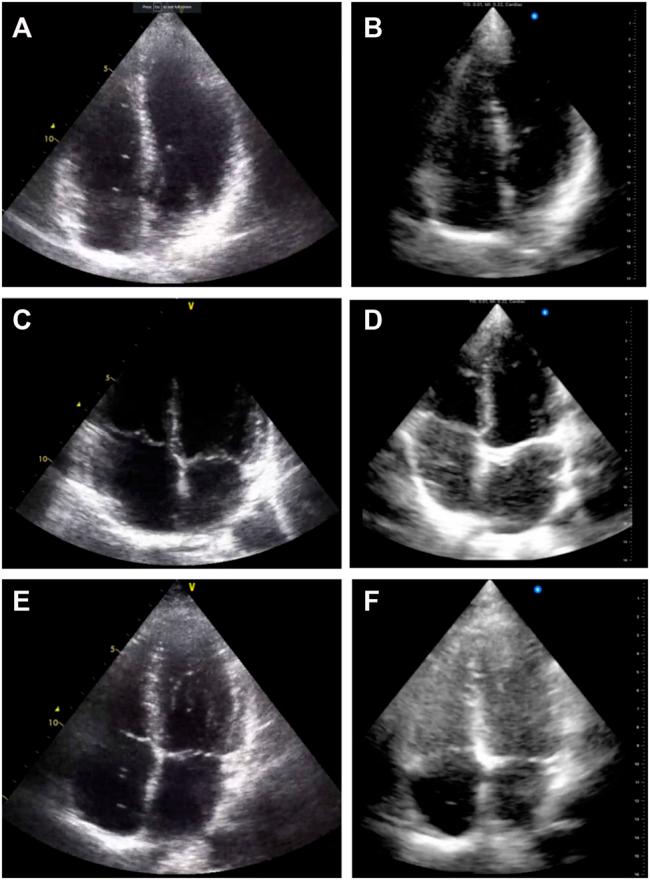

Decompression sickness (DCS) can result from the growth of bubbles in tissues and blood during or after a reduction in ambient pressure, for example in scuba divers, compressed air workers or astronauts. In scuba diving research, post-dive bubbles are detectable in the venous circulation using ultrasound. These venous gas emboli (VGE) are a marker of decompression stress, and larger amounts of VGE are associated with an increased probability of DCS. VGE are often observed for hours post-dive and differences in their evolution over time have been reported between individuals, but also for the same individual, undergoing a same controlled exposure. Thus, there is a need for small, portable devices with long battery lives to obtain more ultrasonic data in the field to better assess this inter- and intra-subject variability. We compared two new handheld ultrasound devices against a standard device that is currently used to monitor post-dive VGE in the field. We conclude that neither device is currently an adequate replacement for research studies where precise VGE grading is necessary.

减压病(DCS)可能源于环境压力降低期间或之后组织和血液中气泡的形成,比如在水肺潜水员、压缩空气作业人员或宇航员身上。在水肺潜水研究中,潜水后通过超声检查可在静脉循环中检测到气泡。这些静脉气体栓子(VGE)是减压应激的一个指标,大量的VGE与减压病发生概率增加相关。VGE在潜水后数小时内常可观察到,并且据报道,个体之间以及同一个体在经历相同的受控暴露时,其随时间的演变情况存在差异。因此,需要小型、便携且电池续航时间长的设备,以便在现场获取更多超声数据,从而更好地评估这种个体间和个体内的变异性。我们将两款新型手持式超声设备与目前在现场用于监测潜水后VGE的标准设备进行了比较。我们得出的结论是,对于需要精确VGE分级的研究而言,目前这两款设备都不足以替代现有标准设备。